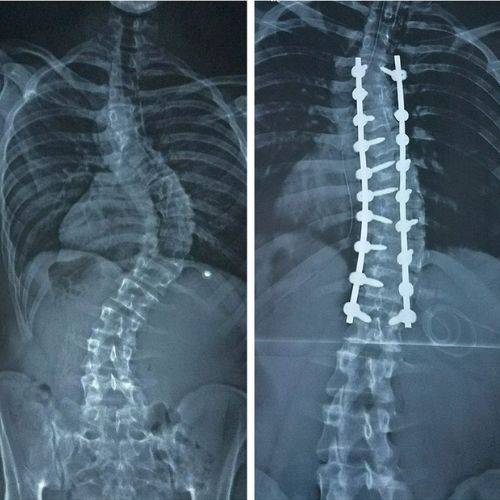

At Stavya: Center for Neck & Back Care, we specialize in advanced treatment for spinal deformities such as scoliosis, kyphosis, and post-traumatic spine imbalances. These conditions can affect posture, movement, and confidence but with today’s precision-based spine correction techniques, we can restore both balance and quality of life. Spinal deformity correction involves carefully realigning the spine using modern surgical methods, fusion techniques, and 3D robotic navigation. Our approach at Stavya is centered on one goal helping patients stand taller, move freely, and live pain-free again.

At Stavya: Center for Neck & Back Care, spinal deformity correction surgeries are performed in our Class 100 modular operation theatres, equipped with robotic navigation, O-arm 3D imaging, neuromonitoring, and bone scalpel systems for maximum precision and safety.

Advanced osteotomy and fusion techniques are used to realign the spine.

Screws and implants are placed under robotic guidance for long-term stability.